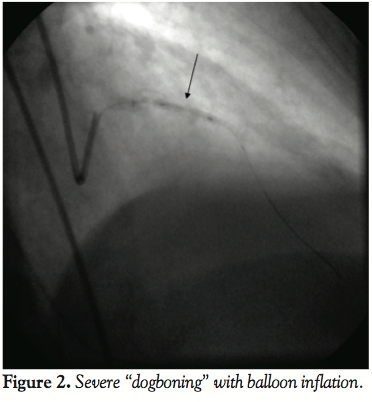

The left main was engaged with a 6 Fr VL 3.0 guiding catheter LAD lesion was traversed with a hydrophilic wire and balloon angioplasty was performed sequentially with a semi-compliant 2.0 x 15 mm balloon and subsequently with 2.25 x 15 mm noncompliant balloons. These demonstrated complete “dogboning” with no plaque fracture (Figure 2). Larger balloons would not cross the lesion site. A cutting wire strategy also did not yield the stenosis and a cutting balloon would not cross. At this point, there was a type B dissection just beyond the lesion site and a glycoprotein IIb/IIIa inihibitor (GPIIb/IIIa) was already administered. The patient still had chest discomfort with improved ST segments, however, and TIMI 2–3 flow. A rotawire would not cross the lesion. An over-the-wire balloon was not available at the time, therefore, a Twin-Pass® catheter (Vascular Solutions Inc.) was utilized, but also would not cross the lesion to allow for wire exchange. Bypass grafting was contemplated, but given the ongoing chest pain and the presence of GPIIb/IIIa inhibitor on board, we pursued a high-risk PCI strategy. More aggressive dilation was performed with 2 separate 2.25 x 15 mm noncompliant balloons to allow passage of a rotawire. Inflations were performed with noncompliant balloons at pressures of 20–24 atm. This resulted in a NHLBI type C dissection with severe balloon “dogboning” (Figure 3).